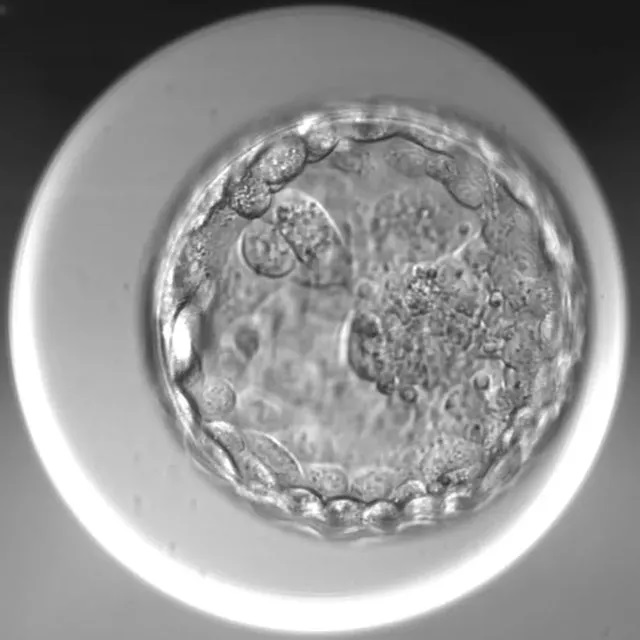

优质囊胚                可用囊胚

所以,哪怕评分蕞高的胚胎也可能是异常的胚胎 (比如染色体异常),而评分低的胚胎也可能是一个正常健康有发育潜能的胚胎。